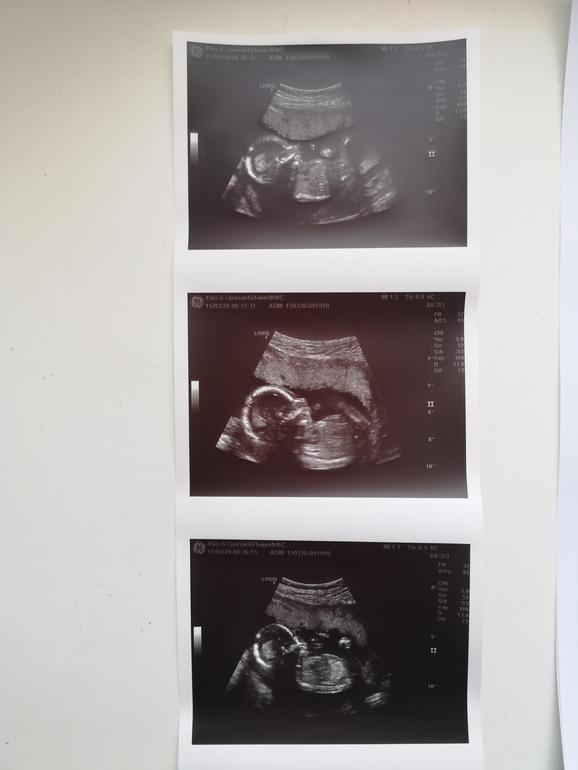

По УЗИ все хорошо, малыш развивается нормально, мы с мужем умилялись, как он там шевелит ручками и барабанит ножками, все органы без особенностей. Матка в нормотонусе и шейка 36.5 мм. Уже второй врач, которому я доверяю больше всех, сказал, что это точно мальчик - так что быть нам родителями трёх сыновей! 🤪🤪🤪 К слову, у меня не было даже какой-то внутренней надежды или предчувствия, что это девочка, поэтому мы даже не удивились)))

Вот фото нашего третьего красавчика, который родится здоровым обязательно!